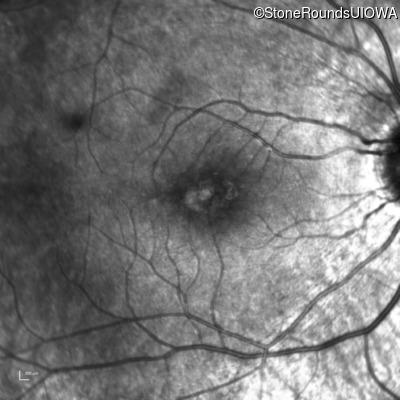

Infrared Fundus Photograph - Right - 20/32 -1

Exemplar